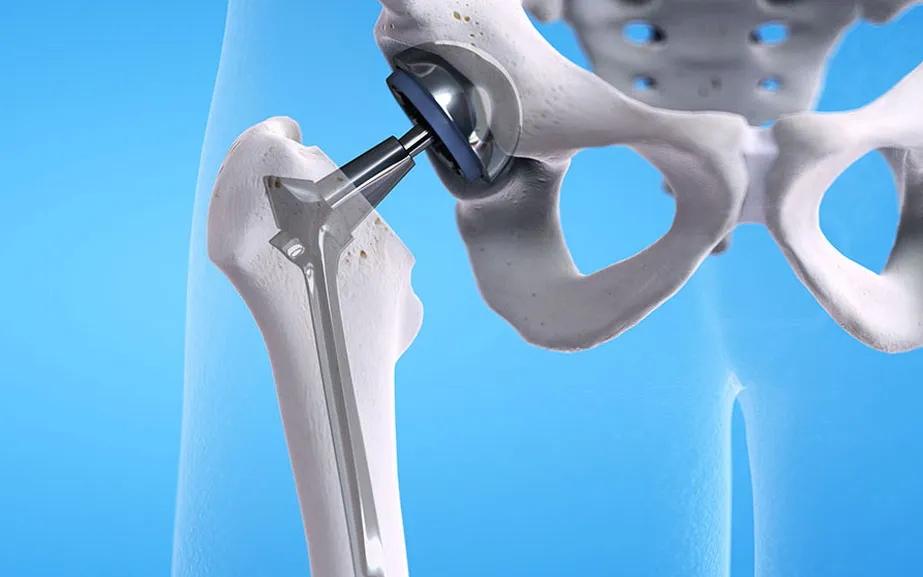

Protez Cerrahisi

Kalça, diz ve diğer eklem protez cerrahisi, eklem replasmanı operasyonları.

Kalça protez cerrahisi sonrası hayat kalitem çok arttı. Dr. Ramin Mirza'nın deneyimi ve yaklaşımı gerçekten profesyonel. Çok memnun kaldım.